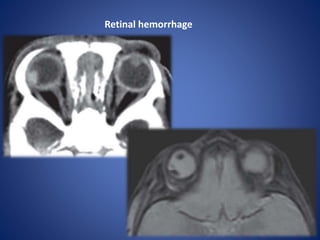

Retinal hemorrhage

• #17 Retinal hemorrhage in a boy less than 1 year old who presented with trauma. - fluid-fluid level